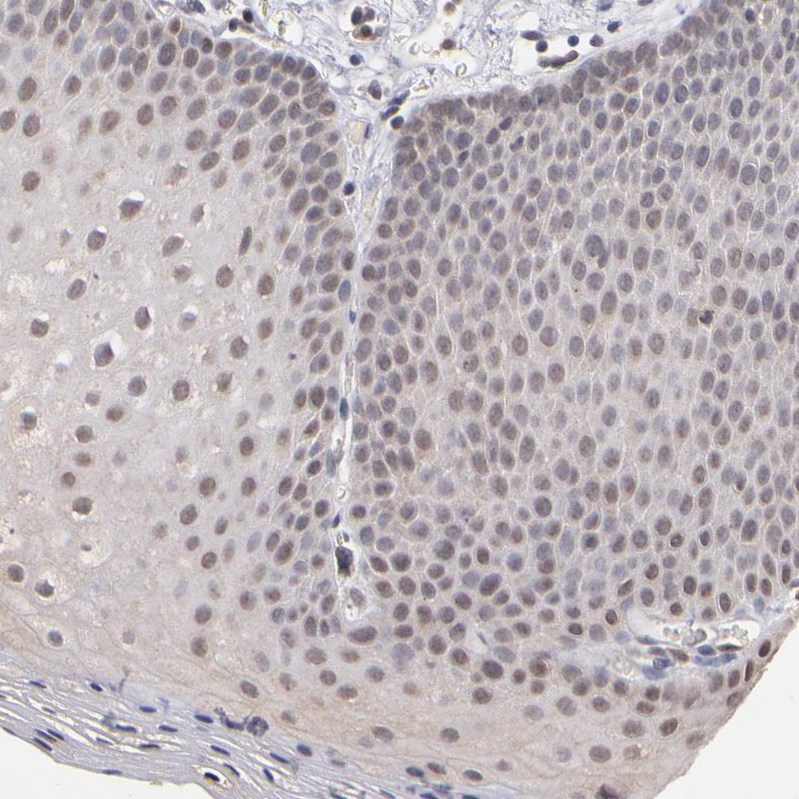

Immunohistochemical staining of human testis shows moderate nuclear and cytoplasmic positivity in cells in seminiferous ducts.